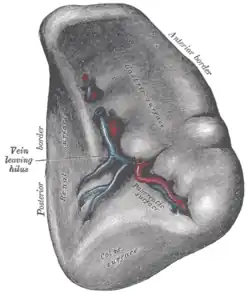

Anatomy

The spleen is underneath the left part of the diaphragm, and has a smooth, convex surface that faces the diaphragm. It is underneath the ninth, tenth, and eleventh ribs. The other side of the spleen is divided by a ridge into two regions: an anterior gastric portion, and a posterior renal portion. The gastric surface is directed forward, upward, and toward the middle, is broad and concave, and is in contact with the posterior wall of the stomach. Below this it is in contact with the tail of the pancreas. The renal surface is directed medialward and downward. It is somewhat flattened, considerably narrower than the gastric surface, and is in relation with the upper part of the anterior surface of the left kidney and occasionally with the left adrenal gland.

Blood supply

Near the middle of the spleen is a long fissure, the hilum, which is the point of attachment for the gastrosplenic ligament and the point of insertion for the splenic artery and splenic vein. There are other openings present for lymphatic vessels and nerves. In addition to the splenic artery, collateral blood supply is provided by the adjacent short gastric arteries.[14]

Transverse section of the spleen, showing the trabecular tissue and the splenic vein and its tributaries

Transverse section of the spleen, showing the trabecular tissue and the splenic vein and its tributaries Spleen